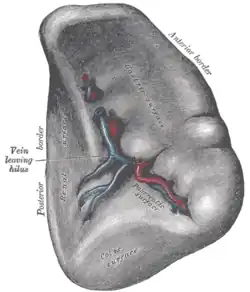

The visceral surface of the spleen. | |